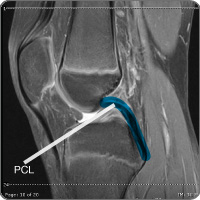

Posterior cruciate ligament injury

cond-pclThe knee contains the posterior cruciate ligament (PCL), which is one of four ligaments (tough bands of tissue) that connect the femur (thigh) bone to the tibia (shin) bone. In combination with the anterior cruciate (ACL), the PCL makes a diagonal "X" through the center of the knee joint and allows the knee to twist/rotate and move side-to-side. The PCL becomes injured or torn when it is stretched beyond its normal range of movement. Research shows that up to 60 percent of PCL injuries may also involve other structures in the knee (meniscus, the pad/disc between the knee bones, cartilage or other ligaments) creating increased instability.